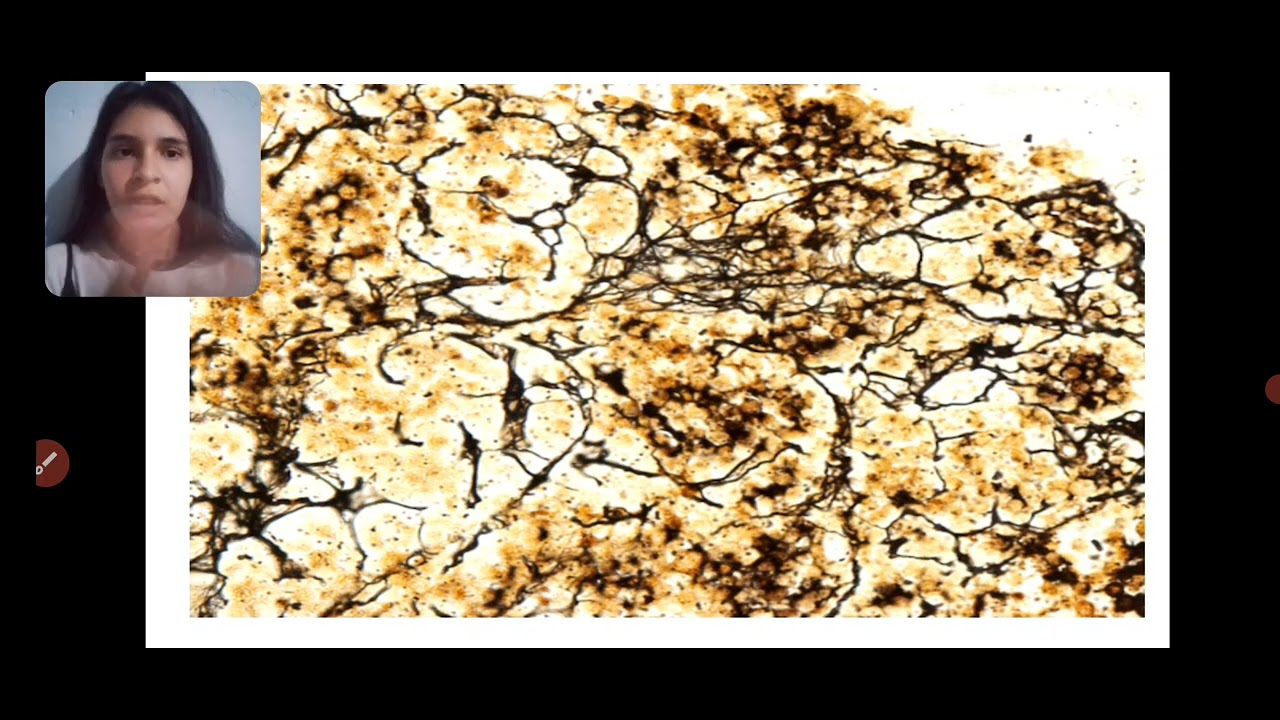

fibras-reticular

• Reticular Fibres 1 год назад

• Las fibras reticulares 5 лет назад

Las fibras reticulares

• Fibras Reticulares 3 года назад

Fibras Reticulares

• 6th week: Reticular fibers, Ag impr. 6 лет назад

6th week: Reticular fibers, Ag impr.